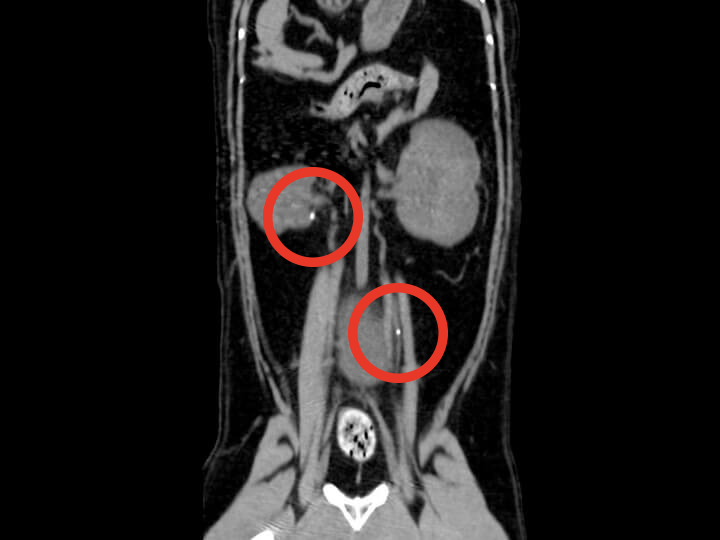

猫の尿管結石 猫の尿管結石

猫の尿管結石とは?

猫の尿管結石は、腎臓と膀胱をつなぐ直径1mm以下の尿管に結石などが詰まる病気です。初期の症状は食欲不振・嘔吐・下痢など非特異的で、片側閉塞の場合、症状が出ない場合もあります。しかし、尿管が完全に塞がると、数日で急性腎不全に陥る非常に危険な病気です。治療介入が遅れると、手術後も腎機能が完全に回復しない可能性もあるため、早期発見・早期治療が重要です。

CT検査だからわかること CT検査だからわかること

CT検査だからわかること尿管結石の初期検査では、レントゲン検査やエコー検査で結石の有無や腎盂の拡張を確認します。これらは健康診断や経過観察には十分ですが、尿管が閉塞して症状がある場合や外科的治療が必要な場合は、より詳細な情報が必要です。

CT検査は、レントゲン・エコー検査では見逃しやすい小さな結石

(1mm前後)の診断に有効です。結石の正確な位置・数、尿の流れを3次元的に把握することで、適応となる治療法(内科/外科)を判断していきます。中には明らかな結石のない尿管閉塞も存在するため、その場合は造影検査なども併用することでより診断の精度を高めます。